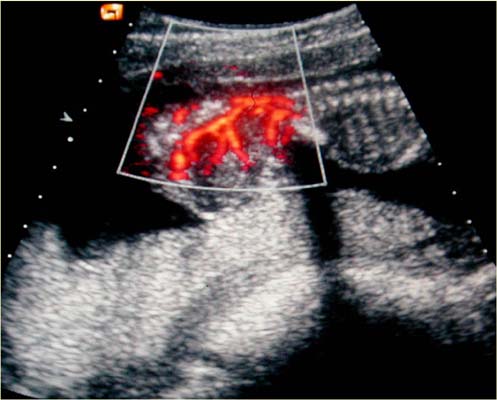

Type II US doppler